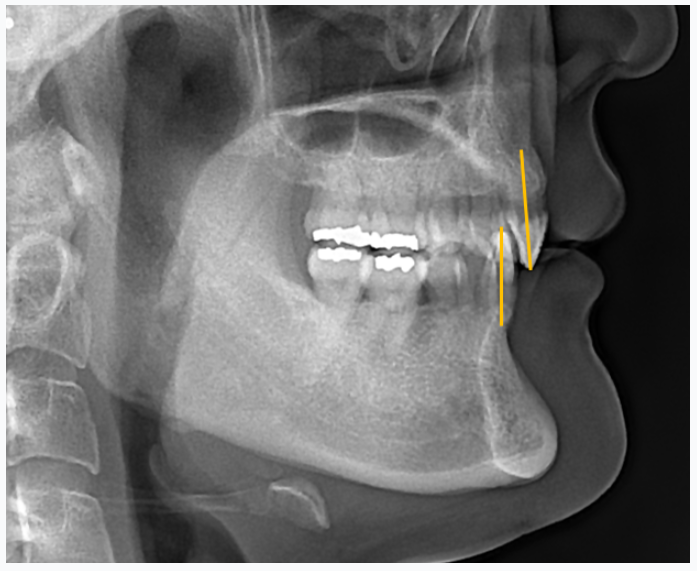

그런 정황을 명확히 보여주는 것은 얼굴 측모의 엑스레이 사진입니다.

상악과 하악의 앞니들이 물리는 관계를 볼 때 쓰는,

치아의 축의 각도가 거의 수직으로 되어 있는 것을 볼 수 있습니다.

노란색 선으로 표시된 부분입니다.

두 선의 각도가 130도 정도되는 걸 정상이라고 봅니다.